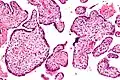

Histomorphologically, VUE is characterized by a lymphocytic infiltrate of the chorionic villi without a demonstrable cause. Plasma cells should be absent; the presence of plasma cells suggests an infective etiology, e.g. CMV infection.

Intermed. mag. Intermed. mag.

High mag. High mag.